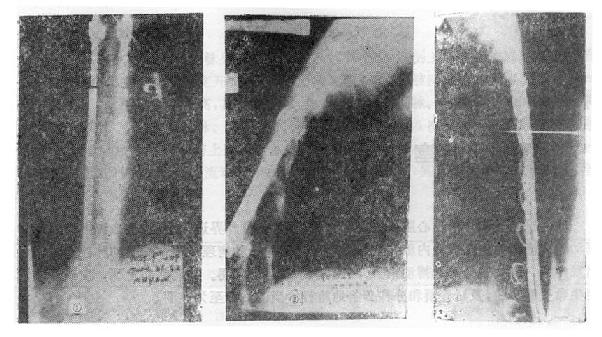

前路手术方法为病人取侧卧位,腰椎骨折由肾切口进入,胸腰段骨折则经切除第10肋之胸腹联合切口进入,结扎节段血管后,切开并向侧方推开椎前胸膜壁层,从腰椎侧方向椎体前方剥离骨膜,先掀起骨膜再进行骨折的处理,有助于防止血管损伤。然后切除骨折处的椎间盘,此时先找出椎间孔前缘,保护好神经和脊髓,再用咬骨钳咬除病椎骨质(保留作植骨用),靠后部分可用电钻磨(图73-14之①②)。对于旋入椎管腔内的骨片,可用刮匙将骨片旋转回原来的部位,减除脊髓的压迫(图73-14之③)。直至看到对侧硬脊膜,然后进行植骨。取一段腓骨嵌入植骨,在一助手将脊柱由后向前推顶的同时,将腓骨卡入,恢复椎体前缘高度(图73-14之④)。然后在植骨块的两侧再植入一些松质骨。

图73-14 前路手术治疗旋转型脊柱骨折

①剥离骨膜②咬除病椎骨质;③使骨片复位;④植骨